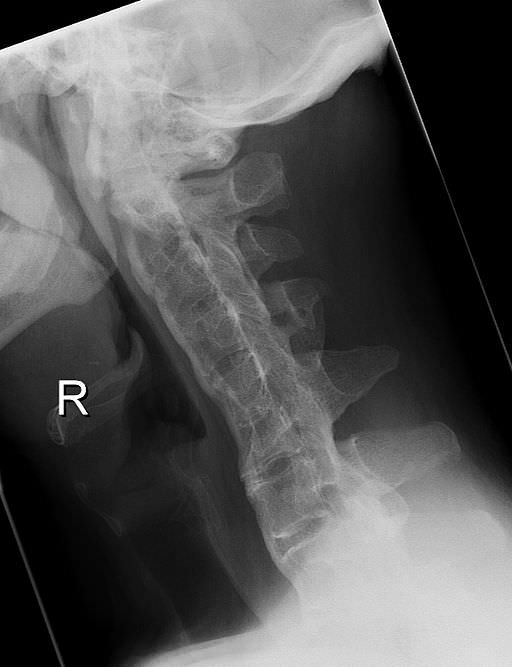

Een gevaarlijk stijve nek bij ziekte van Bechterew Nederlands Rug Ziekte Van Bechterew Na de rugwervels raken ook de gewrichten van. de ziekte van bechterew begint met pijn en stijfheid, vooral laag in de rug. de ziekte van bechterew wordt ook wel axiale spondyloartritis genoemd. Chronische pijn en stijfheid in het midden van de rug en soms over de hele rug, vaak gepaard gaand met uitstralingspijn naar de bil. wanneer. Rug Ziekte Van Bechterew.